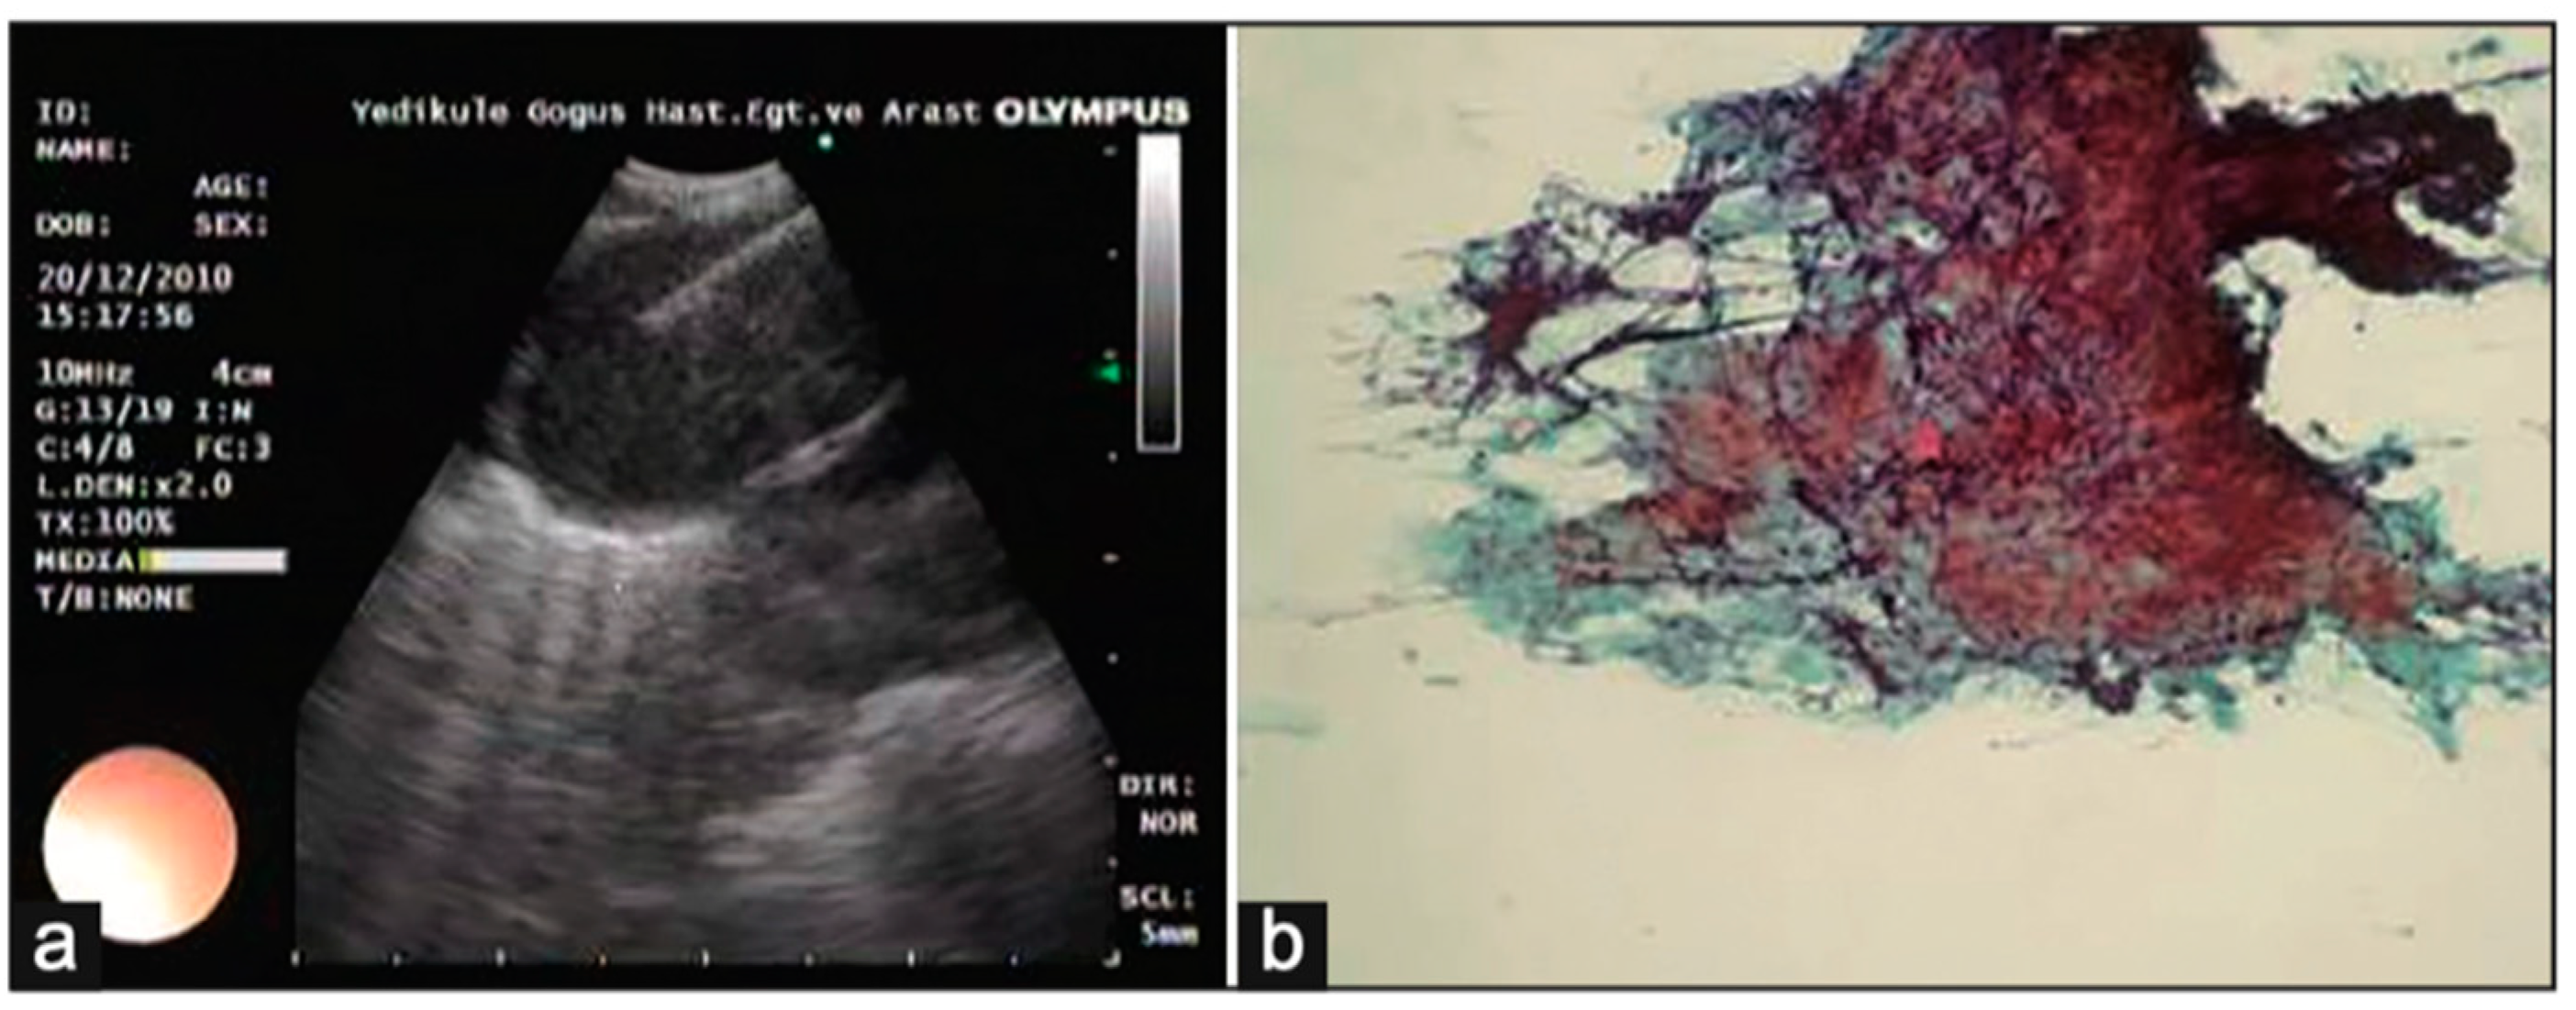

Ultrasound has emerged as an essential tool for the assessment of pleural abnormalities and the therapeutic drainage of air or fluid. Ultrasound machines use transducers that emit ultrasound waves with specific frequencies and wavelengths. These waves penetrate tissues and reflect back to create a 2-D image. The time taken for waves to return determines the distance of structures. Air and bone have high attenuation coefficients, making it very difficult to form images. Conversely, fluid has a very low attenuation coefficient, which is great for pleural effusions. A transducer has a specific frequency attached to it. A high frequency (7.5–12 MHz) is used to image shallow structures like the chest wall and the parietal pleura. A low-frequency transducer (2–5 MHz) is used for deeper structures, like pleural effusions and the diaphragm. Most of the time, an ultrasound of the chest is performed by a clinician interested in answering a diagnostic query. The ultrasound beam needs to pass through the rib spaces, which can be challenging, and this is why patient positioning is crucial to optimizing image acquisition. There are three different imaging modes a clinician may use when performing an exam. The B-mode (brightness mode) is the most common mode used. It provides a grayscale image and allows for real-time procedural guidance. The M-mode (motion mode) provides a one-dimensional image showing movement over time. This mode is useful for pneumothorax evaluation and assessing pleural apposition presence or absence. Finally, the Doppler mode adds color images to the grayscale image so that the clinician may identity blood vessels, blood flow direction, or other moving fluids. This mode is particularly helpful when performing a thoracentesis and identifying intercostal vessels to avoid. Thoracic ultrasound has several advantages. It is mobile, so the clinician can bring this technology to the patient. Because it allows for real-time invasive procedural guidance, an improved safety profile is associated with pleural procedures. Finally, thoracic ultrasound is more sensitive than CT in detecting pleural fluid characteristics, such as septations (Figure 6) [28]. Knowing that an effusion is multiseptated is important for guiding therapeutic decisions. Real-time thoracic ultrasound can allow for the precise placement of chest drains into the largest locule, optimizing treatment and outcomes.

Figure 6. Pleural ultrasound revealing septations. Reproduced from Hassan et al., 2020 [28]. Shared under the terms of the Creative Commons Attribution Non-Commercial Licence 4.0. See: https://creativecommons.org/licenses/by-nc/4.0/.